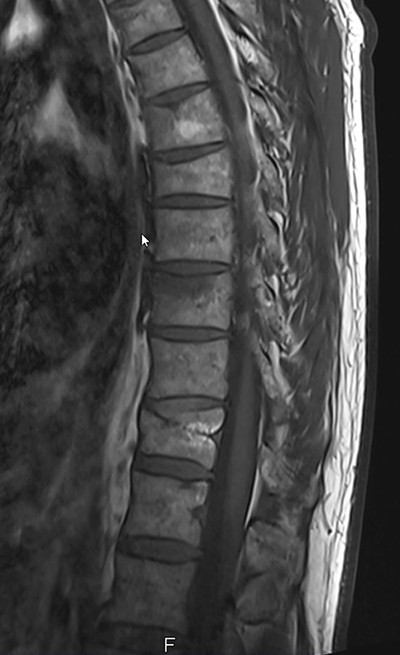

Die Abklärung erfolgt mittels Knochendichtemessung, wobei standardmässig eine DXA (dual-energy X-ray absorptiometry) durchgeführt wird. Die DXA wird nur unter gewissen Voraussetzungen (an nur einer Messregion) durch die Krankenkassen übernommen (Tabelle 1). Weiter ergänzen wir bei älteren Patienten oder Grössenverlust eine Morphometrie, um asymptomatische Wirbelkörperfrakturen nicht zu verpassen (gut 2/3 aller osteoporotischen Wirbelkörperfrakturen sind asymptomatisch!).